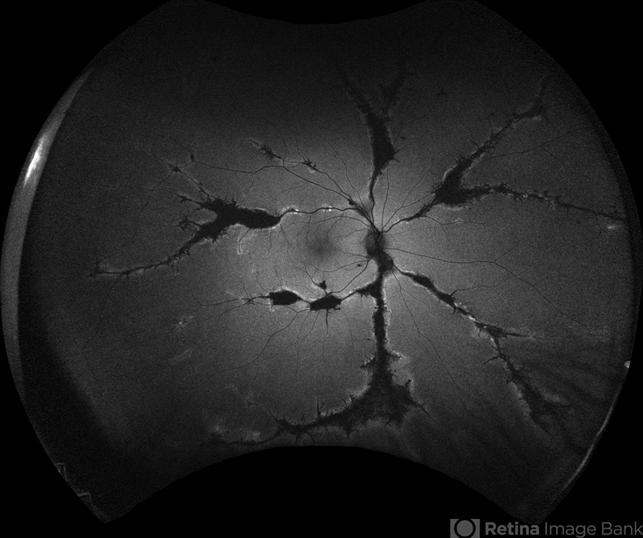

- pigmented paravenous chorioretinal atrophy (PPCRA)

- Fundoscopy of a 42-year-old asymptomatic man with pigmented paravenous chorioretinal atrophy. Pigmented paravenous retinochoroidal atrophy (PPRCA) is a rare disorder of unknown etiology. The disease is characterized by pigment accumulation along the distribution of retinal veins. The findings are usually incidental with minimal effect on vision.